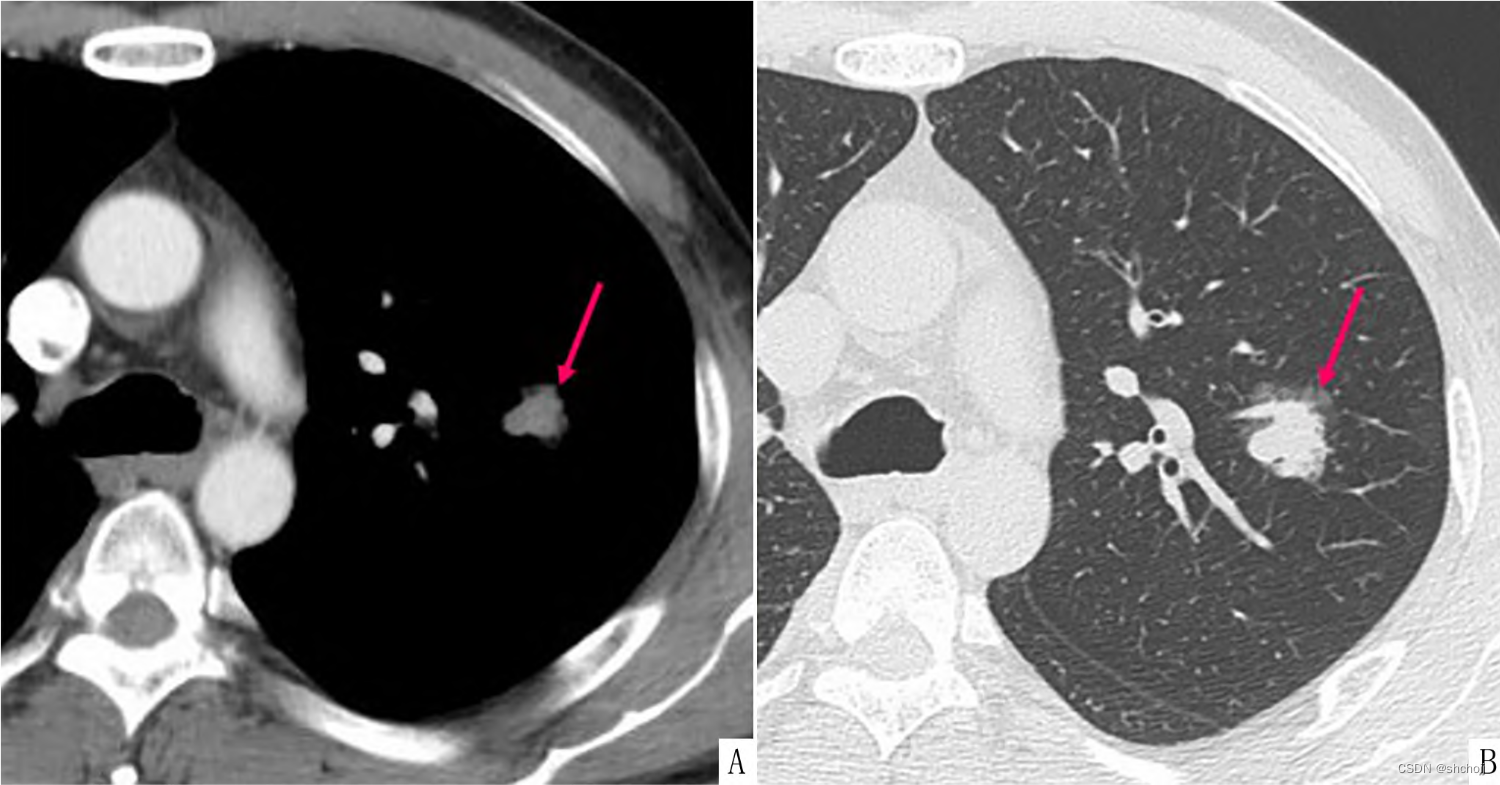

纵膈窗(A)、肺窗(B);不同窗宽窗位